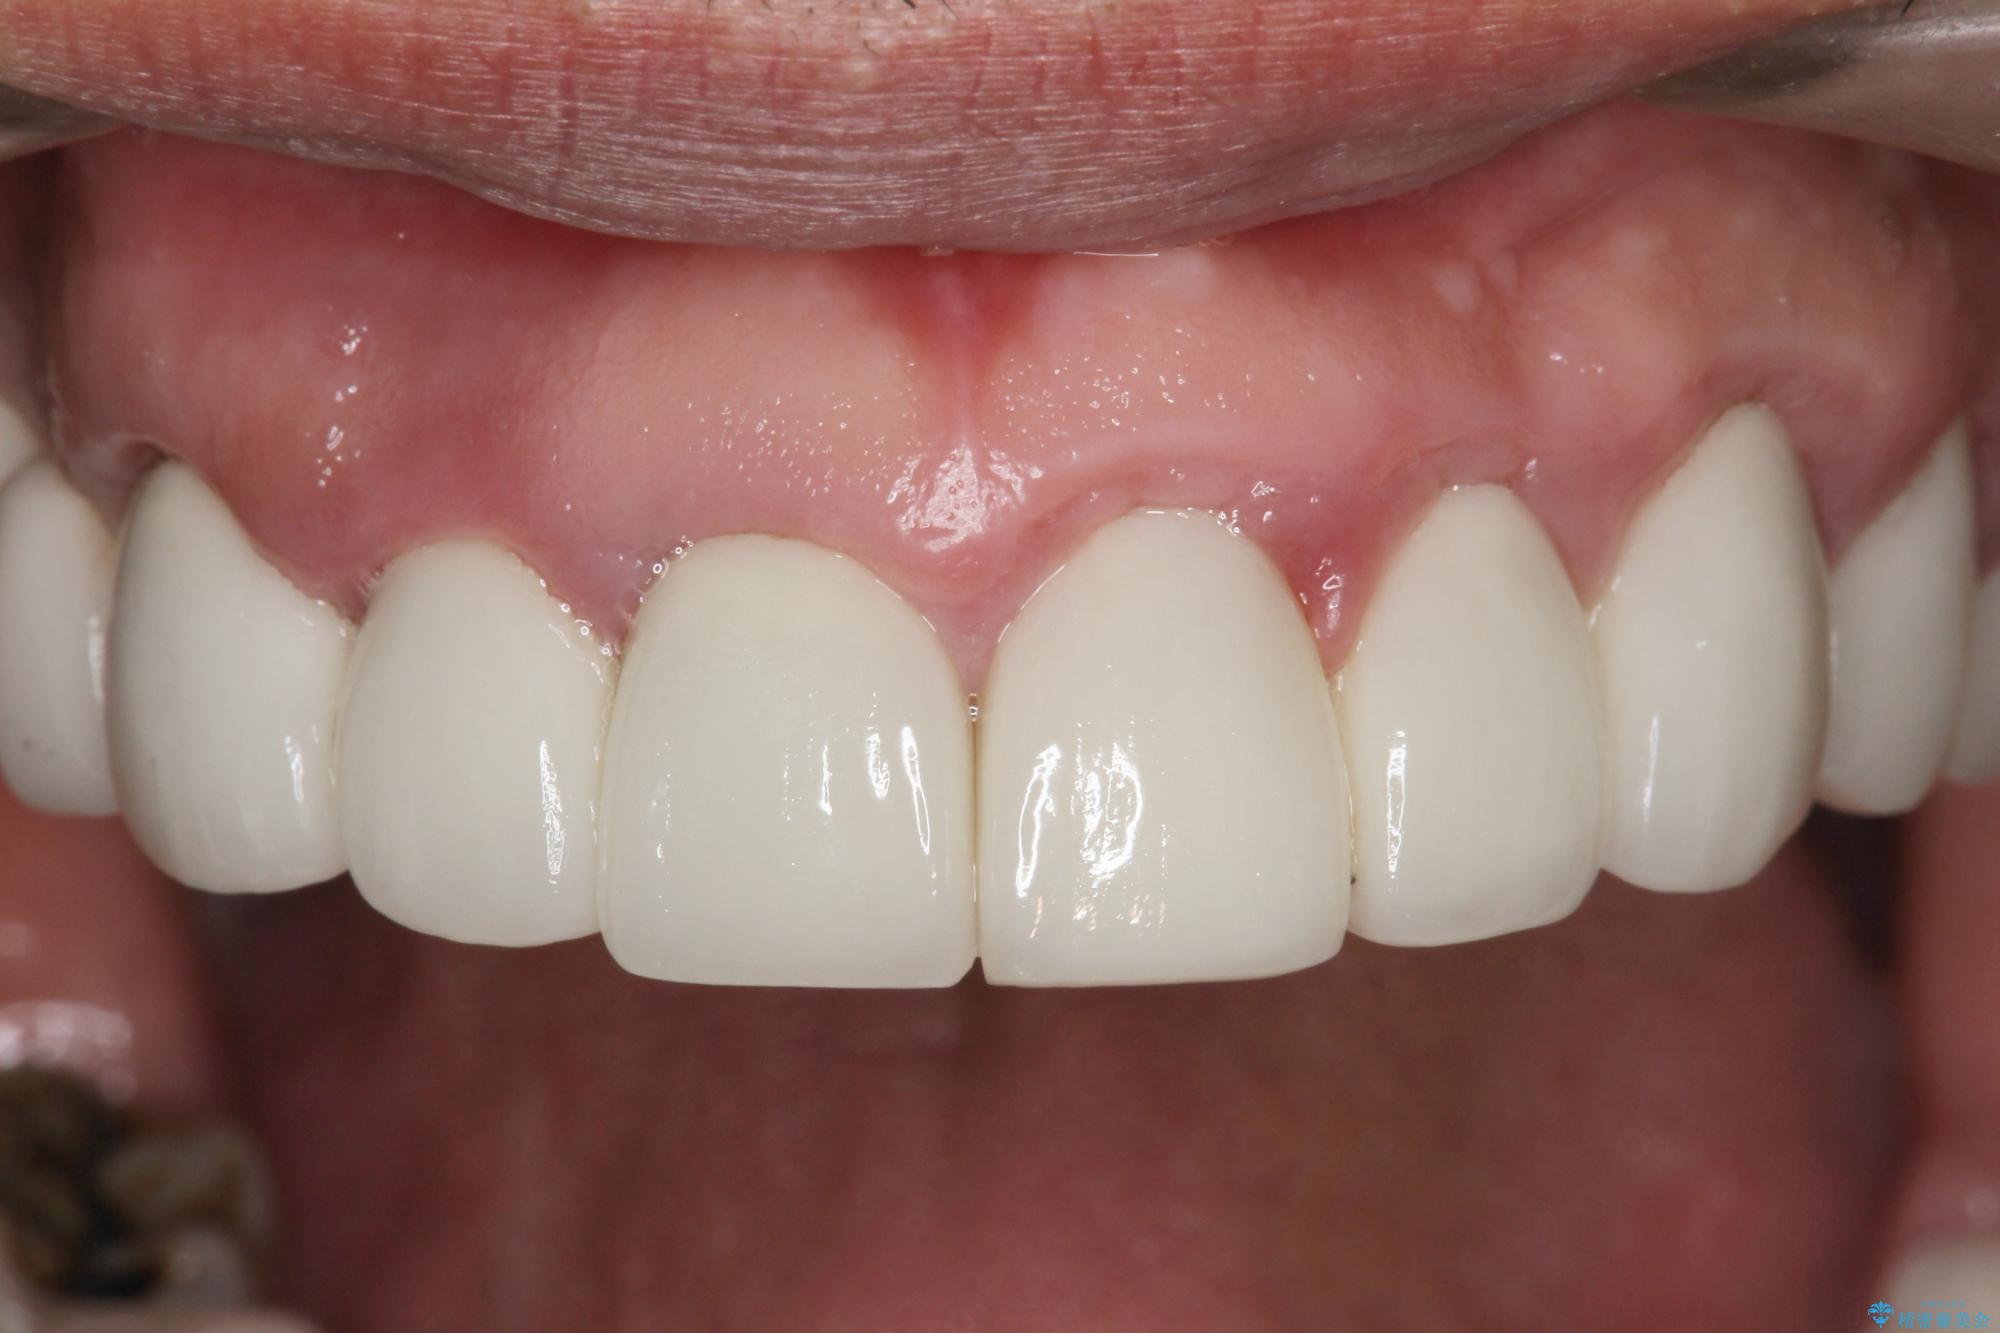

[ 歯周外科手術 ] セラミック治療後の歯ぐきの違和感

- 「セラミック治療を他院で受けたが、それ以来歯ぐきが腫れ違和感がある、改善してほしい。」と歯ぐきの状態改善を希望され来院されました。

セラミッククラウンを除去し仮歯を装着し、歯周外科手術を行い歯ぐきの状態を改善したのち、適合の良いセラミッククラウンを再作製をする治療計画としました。

- 90.2万円(ジルコニアクラウン×6・仮歯×6 ・歯周外科手術)費用は治療当時の料金となります

見た目の良いクラウンが装着されていても、歯ぐきの状態が悪ければ違和感や歯ぐきの腫れ、臭いの元となっていることが多く見られます。